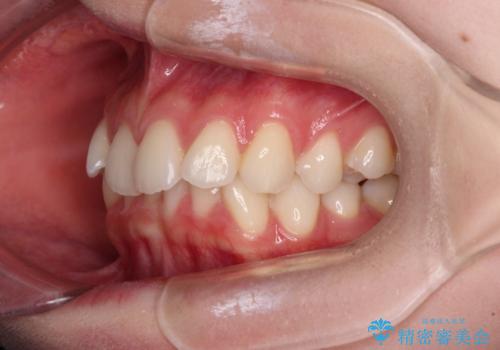

前歯のデコボコと深い咬み合わせ インビザラインできれいに改善

- 前歯のデコボコと下の前歯が隠れてしまう咬み合わせを気にして来院された患者様です。

インビザラインによる上下歯列の拡大と、IPR(歯と歯の間を削る)にるスペースの獲得により、口元のデコボコとディープバイトを改善することとしました。